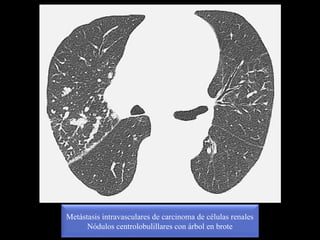

Metástasis intravasculares de carcinoma de células renales

Nódulos centrolobulillares con árbol en brote